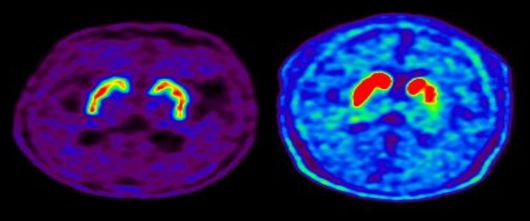

정상인의 뇌 핵의학 영상(도파민 분비 부위 활성·왼쪽)과 파킨슨병 환자의 뇌 핵의학 영상(도파민 분비 부위 퇴화). |

이산화질소 외에 미세먼지(초미세먼지 포함), 오존, 이산화황, 일산화탄소는 파킨슨병 발생과 통계학적으로 유의미한 연관성을 보이지 않았다. 파킨슨병은 대표적인 퇴행성 뇌질환으로 신경전달물질인 도파민을 비롯한 다양한 뇌 신경세포가 사멸하여 떨림, 경직, 보행장애와 같은 운동 증상과 치매, 망상, 우울증, 자율신경장애, 수면장애 등의 비운동 증상을 보인다. 발병 원인은 정확히 규명되지 않았으나 최근 들어 유전적 요인과 더불어 살충제, 제초제, 금속, 기타 독성 물질 등 환경적 요인도 파킨슨병의 중요한 유발 인자로 제시돼 왔다.